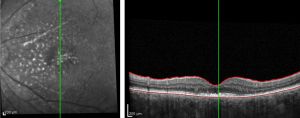

As outlined above in the ‘Diagnostic Studies’ section, evaluation of uveal lymphoma includes ultrasonography, angiography and high resolution neuroimaging. B-scan ultrasonography allows for evaluation of the posterior segment of the eye. Findings are not specific, but can aid in narrowing the differential diagnosis and identifying ESE.[18] OCT imaging can also be beneficial in diagnosis and often reveals a lumpy bumpy choroid as seen in image 4.

Angiography can help to localize the layer that the infiltrates reside and can show hypofluorescent areas due to the blocking effect of sub-RPE masses. If RPE atrophy has occurred, hyperfluorescent areas may be seen.[19] It has been noted that ICG is the preferred form of angiography for uveal lymphoma over fluorescein angiography (FA) as ICG yields more reproducible findings.[1][20]